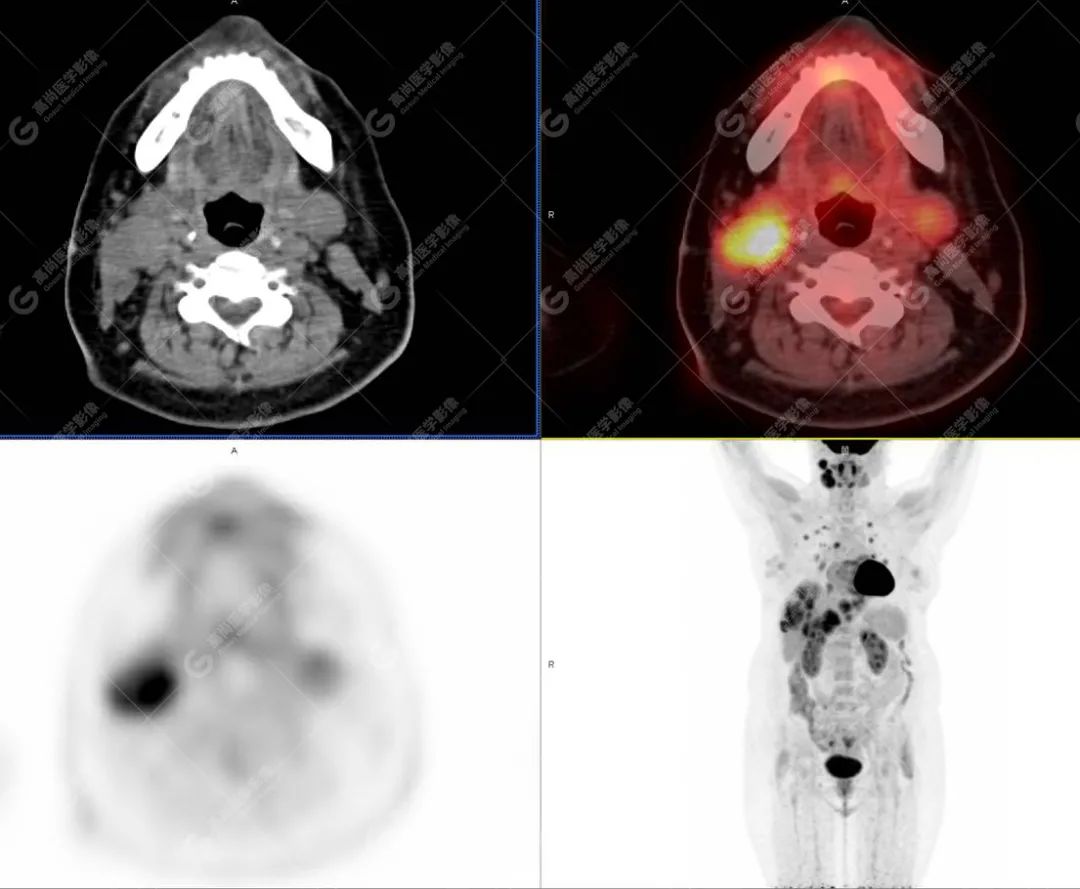

影像诊断:1. 结合病史,右颈部神经鞘瘤(低度恶性)术后改变,右侧颈部稍低密度及等密度结节,代谢异常增高,考虑为肿瘤复发并右颈部淋巴结转移,建议活检。 2. 双侧肺门及纵隔(4R 区)多发肿大淋巴结,代谢异常增高,考虑为转移。 3. 双肺多发大小不等实性结节,部分代谢增高,考虑为转移。 4. 肝脏多发低密度结节及肿块,代谢异常增高,考虑为转移。 5. 右侧第 8 前肋骨骨质破坏,代谢异常增高,考虑为转移。

随访病理(右侧颈部结节):血管肉瘤